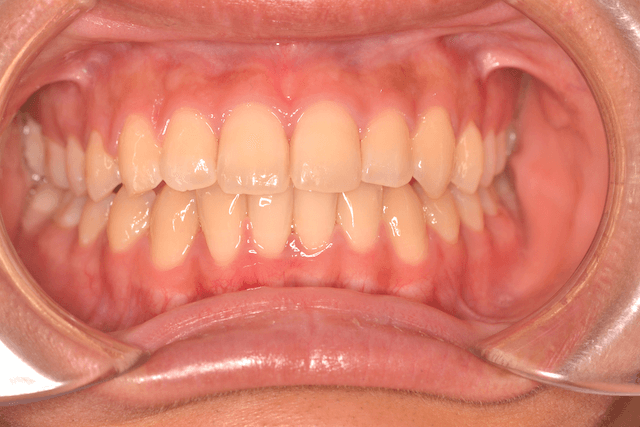

叢生をフルDBSで改善した症例

※DBSとはダイレクトボンディングシステムと呼ばれており、ブラケットにワイヤーを通して歯を動かしていく矯正治療です。

患者情報

21歳女性

主訴

ガタガタしている

行った治療内容

フルDBS

治療のリスク

歯肉退縮、歯根吸収

治療期間

動的治療期間2年4か月

※ クリックして拡大することができます。